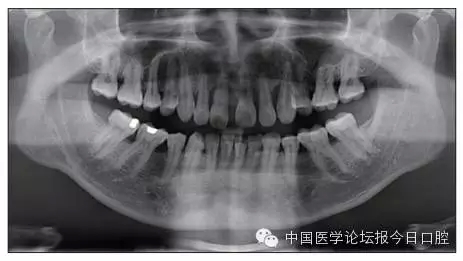

X線檢查

全口曲面體層片(圖3)顯示,患者全牙列牙槽骨吸收;根尖片(圖4)示11近中牙槽骨角形吸收已達(dá)根尖1/3,21牙槽骨嵴頂吸收至根1/2,23牙槽骨近中骨板角形吸收至根1/2。磨牙區(qū)骨嵴頂吸收3mm。治療前頭顱側(cè)位片見(jiàn)圖3,治療前ODS模型見(jiàn)圖5。

圖3 治療前頭顱側(cè)位片及曲面體層片